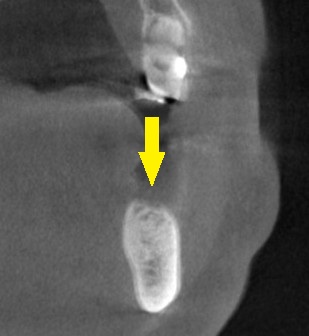

3か月ほどして、CTを撮影してみると、下の写真2段目のように、大きく骨欠損となっていました。

2本のインプラント埋入を目指したいのですが、2本目の部位では、下方に通っている神経までの距離は3~4mm程度でした。

ショートインプラントでも厳しいので、この場合は、人工骨を用いて、上方に骨を増やす手術を併用する計画としました。